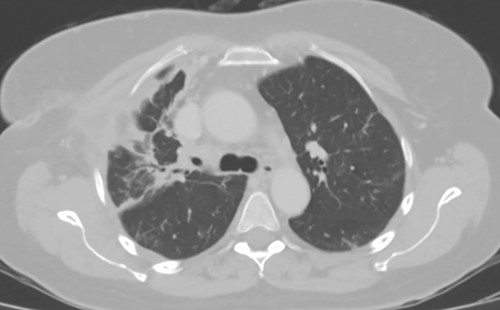

As the patient lived several hours away from the closest hospital, we obtained a second post-operative chest CT to ensure that she had no additional collections and to establish a new baseline. This demonstrated a 4 cm collection in the subcutaneous space. We aspirated the fluid, which showed no growth. The patient was discharged on a course of oral moxifloxacin. A repeat chest CT 4 weeks after Clagett closure was obtained and showed improved aeration of the right upper lobe (Fig. 4).